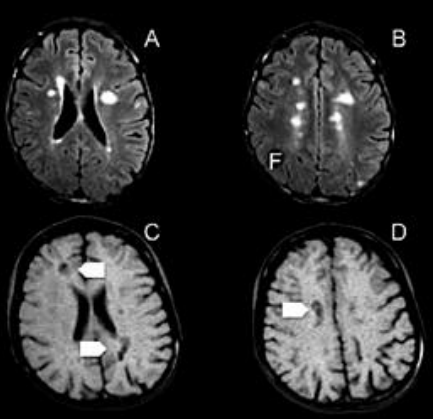

Observe a imagem abaixo. Mulher de 44 anos de idade se apresenta com dor.

A respeito do diagnótico mais provável, assinale a alternativa correta.

As imagens da ressonância abaixo são sugestivas de: